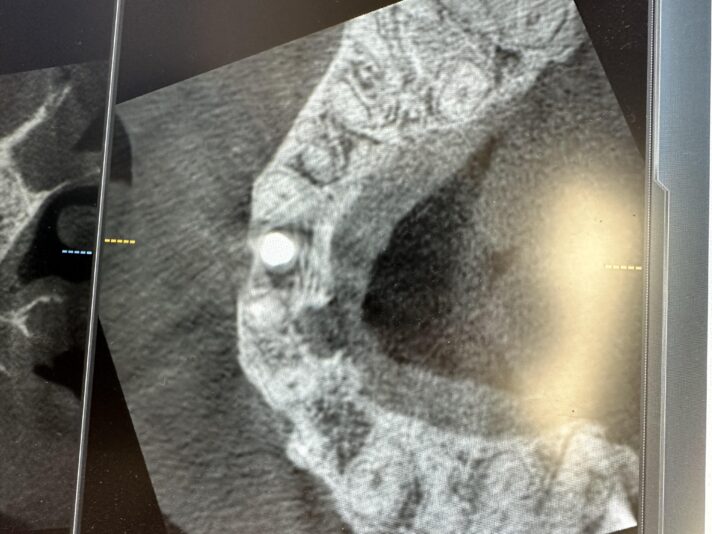

• This case was a tricky one. Sometimes, we just need to do the best with what our patients anatomy gives us. Patient was referred to me wanting an implant and there wasn’t much to work with and oh yeah, the mental foremen was smack dab in the middle of our sight.

With the help of some buccal plate decorticating, a tenting screw, and some CGF/PRF…